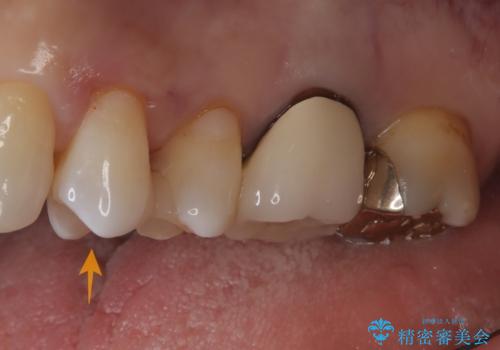

- 奥歯の被せ物が欠けたを主訴に来院された患者様です。欠けてしまった被せ物を除去後セラミックインレーで治療を行いました。

欠けた範囲が大きく被せ物を外して後、セラミックインレーで治療を行いました。欠けたままの状態を放置しているとそこに食べ物が詰まり虫歯になってしまうので早めの治療が必要です。